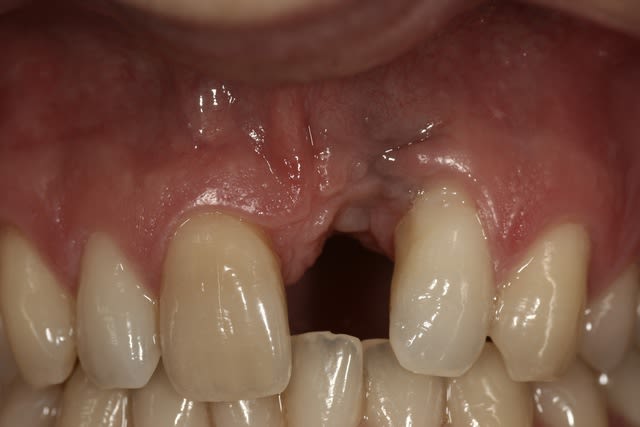

Juste parce que c'était le 1er, et que le résultat est plutôt flatteur...malgré le 3/0.

J'ai pas de photos de la chir elle-même, et ça tient plus du conjonctif enfoui que du pédiculé.

Exact, l'implant y est déjà ; avec une belle inclinaison mésio-distale.

Je ne gère "que" la partie prothétique, et c'est plutôt le côté mésial de 22 qui me pose problème.

Si vous avez des idées pour éviter les bourrages alimentaires?

Les 2 centrales avaient été expulsées suite à un choc, réimplantées et seule la 21 n'a pas tenu.